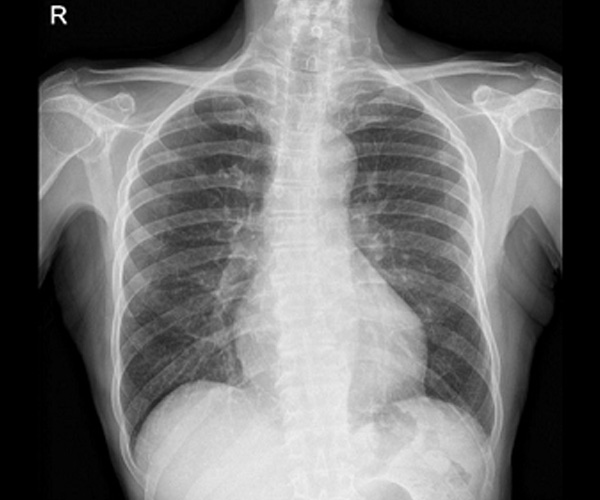

Dopo 3 giorni dalla dimissione si ripresentava in Pronto Soccorso per ricomparsa di febbre. Il tampone antigenico per COVID-19 risultava negativo, mentre l’Rx torace evidenziava l’aumento del disegno interstiziale (Figure 1 e 2).

Figura 1. Rx torace

Figura 2. Rx torace laterale

In alcuni pazienti con infezione disseminata da BCG, la radiografia del torace o la tomografia computerizzata (TC) mostrano un pattern nodulare o interstiziale miliare, talvolta associato ad adenopatia ilare; questi rilievi sono osservati più frequentemente in associazione con sepsi [10,45]. La sensibilità della radiografia del torace è limitata; in una serie comprendente 216 pazienti con infezione sistemica da BCG, la radiografia del torace non è riuscita a rivelare un pattern miliare in circa il 25% dei pazienti con polmonite successivamente identificata tramite TC [8].